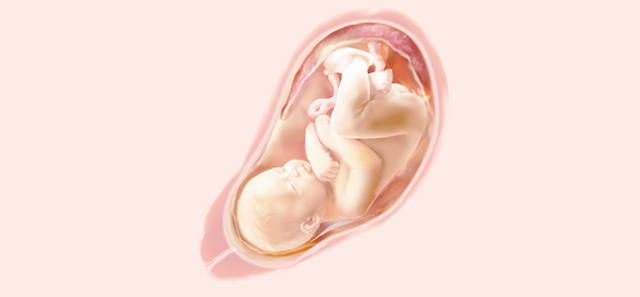

La posición habitual es semi flexion

• SEMANA 18

SEMANA 18